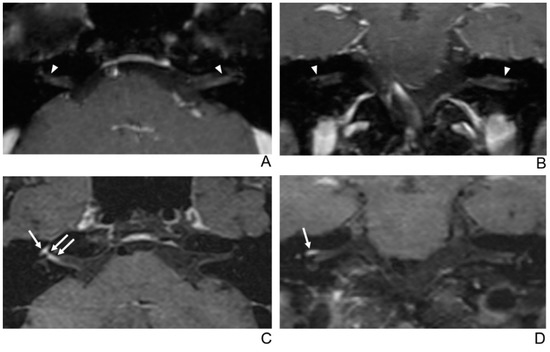

Figure 3.

A 29-year-old male patient with left facial neuritis. (A–D) Paired axial and coronal CE-GRE (A,B) and T1 BB-FSE (C,D) images of the same patient. The left distal canalicular segment of the facial nerve showed faint enhancement in the axial (A) and coronal (B) CE-GRE images (arrowheads). Those images were interpreted by reviewers 1 and 2 as suspicious left facial neuritis (1, diagnostic confidence; 1, 0, and 1, visual grades for contrast enhancement (CE) in the canalicular, labyrinthine, and anterior genu segments, respectively). In contrast, the left facial nerve shows asymmetric, intense enhancement in the canalicular, labyrinthine, and anterior genu segments in the axial (C) and coronal (D) T1 BB-FSE images (arrows); it was evaluated by reviewers 1 and 2 as left facial neuritis (2, diagnostic confidence; 3, visual grade for CE in all three segments).